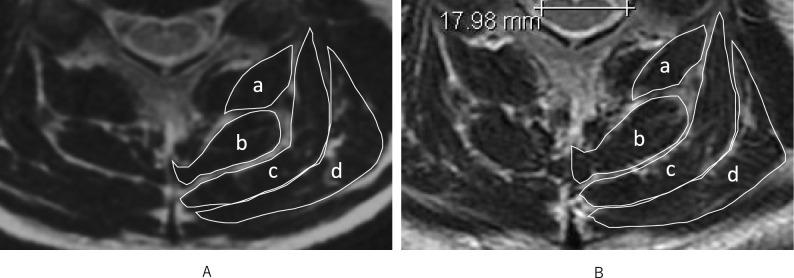

Few studies have investigated long-term changes in the posterior extensor muscles of the cervical spine in healthy subjects. Therefore, we used MRI to investigate changes in the posterior extensor muscles in healthy subjects over 20 years. The subjects of this study were 55 volunteers with an average follow-up period of approximately 20 years. The axial images of the C3/4, C4/5, and C5/6 levels from the initial scan and scans taken 20 years later were evaluated and compared for the following: the cross-sectional areas (CSAs) of the multifidus, semispinalis cervices, semispinalis capitis, and splenius capitis muscles, along with left-right differences, gender differences, influence of age, and muscle fatty degeneration of each muscle. The mean CSAs of the posterior extensor muscles significantly increased at C3/4 and significantly decreased at C5/6 over 20 years. The CSA of posterior cervical extensor muscles always tended to be greater on the left side than on the right side and was significantly larger in men than in women at all levels. The fatty degeneration increased significantly at all intervertebral levels. The decrease in the CSA was significantly associated with smoking status (relative risk: 2.19, 95% confidence interval: 1.32-3.63, p < 0.01), but not with clinical symptoms.

很少有研究调查健康受试者颈椎后伸肌的长期变化。因此,我们使用磁共振成像(MRI)来研究健康受试者在20年期间后伸肌的变化。本研究的受试者为55名志愿者,平均随访期约为20年。对初始扫描以及20年后扫描的C3/4、C4/5和C5/6水平的轴向图像进行评估,并比较以下内容:多裂肌、颈半棘肌、头半棘肌和头夹肌的横截面积(CSA),以及左右差异、性别差异、年龄影响和各肌肉的脂肪变性。20年间,后伸肌的平均CSA在C3/4水平显著增加,在C5/6水平显著降低。颈椎后伸肌的CSA在左侧总是倾向于大于右侧,并且在所有水平上男性均显著大于女性。所有椎间水平的脂肪变性均显著增加。CSA的降低与吸烟状况显著相关(相对风险:2.19,95%置信区间:1.32 - 3.63,p < 0.01),但与临床症状无关。